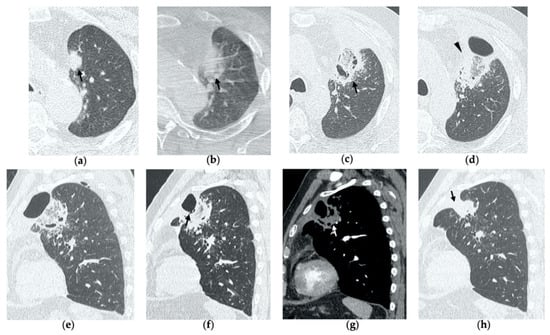

Figure 7. 68-year-old man with a biopsy-proved squamocellular carcinoma in the left upper lobe. (a) Axial CT before treatment. (b) Cone-beam CT image at the end of MWA shows a wide GGO area (black arrow) among the ablation site. (ce) Since persistent hydro-pneumothorax on chest X-rays is detected, CT without contrast administration is performed before the usual 1-month follow-up; axial and sagittal CT images show a large consolidation with central cavitation (black arrow); on a different level, a concomitant hydro-pneumothorax is evident (arrowhead); the diagnosis of broncho-pleural fistula is made. (f,g) Sagittal 2-month follow-up CT images show a decrease in size of the cavitated consolidation and hydropneumothorax; a communication between a bronchus and the pleural cavity is evident (black arrow); (f) the consolidation shows no contrast enhancement (white arrow). (h) Axial 4-month follow-up CT image shows a decrease in size of the consolidation with complete resolution of both cavitation and pneumothorax (black arrow).

5. Early Complications

The most common complications to consider after lung MWA are pneumothorax (38%), pleural effusion (3–6%) and parenchymal hemorrhage (3–6%), which in most cases present a benign course without any consequences for the patient [7,10,14,21,25]. Since these represent frequent findings in clinical practice in most hospitals, we decided to describe a rare complication (0.5%) that often risks being overlooked: bronchopleural fistula (BPF) [25].

BPF is defined as communication between a bronchus and the pleural space through the ablation zone (Figure 6e,f). The management of this complication is challenging, since treatment may require insertion of a percutaneous drainage or eventually surgery, bronchoscopic or interventional procedures. As a result, BPF represents an extremely rare though potentially severe complication and it should be suspected in cases of delayed or persistent pneumothorax, detected with chest X-ray, respectively, during early and late follow-up CTs (Figure 7) [26].

BPF commonly occurs with hydropneumothorax, and it should not be mistaken with a bronchial fistula, which is a communication between a bronchus and a cavitation in the ablation area and usually resolves uneventfully [26].